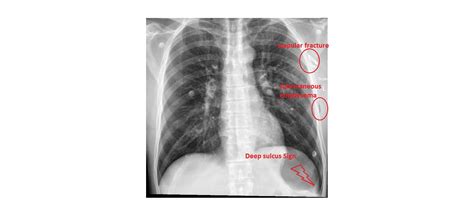

The BMJ

Deep sulcus sign in chest trauma | The …

Deep sulcus sign | Emergency Medici…

ResearchGate

(PDF) Deep Sulcus Sign